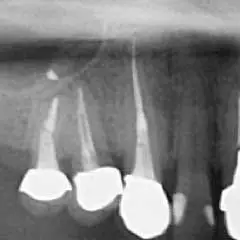

下の写真をご覧ください。歯の中にある黒い部分が「根管」です。これを残さず取り除く必要があるのですが、ご覧の通り根管の形状は非常に複雑です。除去が不十分なまま治療を終えてしまうと、残された虫歯菌が繁殖し、再び痛みを引き起こしてしまうのです。

他院では抜歯と診断されてしまった歯でも、当院では抜歯せずに処置した症例も多数あります。次の画像をご覧ください。黒い影が出ている部分が問題の箇所で(根尖病変)、治療後はこの影がなくなっているのが見てわかります。

根尖病変を治療した症例。